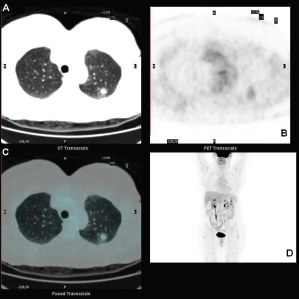

Standard F18-fluorodeoxyglucose (18F-FDG) computed tomography–positron emission tomography (CT–PET) scan was performed and showed a mildly metabolitically active lesion suspicious for hamartoma or pulmonary metastases. At this site, the maximal standardised uptake value corrected for body weight (SUV bw_max) was 1.2 (Figures 1a–d).

Figure 1. FDG-PET showing the pulmonary lesion in the upper lobe (a) transaxial low dose CT image, with midly increased metabolism (b) transaxial PET image, fused transaxial section and maximum intensity projection image (c and d).